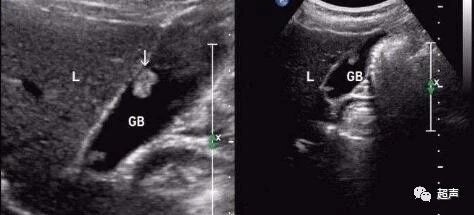

胆囊腺瘤多为单发,有蒂,外形可呈乳头状或非乳头状,恶变率约30%,癌变机会与腺瘤大小呈正相关,是胆囊最常见的良性肿瘤,女性比较多见,男女之比约2: 7,大多数为单发,少数多发,可发生在胆囊的任何部位,合并急性胆囊炎时可出现右上腹阵发性胀痛或绞痛、恶心、呕吐等症状,直径大于1cm或直径大于5mm且进行性增大的胆囊腺瘤应行手术治疗,药物治疗不能消除胆囊腺瘤。

简单来说,反复发作急性胆囊炎或慢性胆囊炎症状(右上腹隐痛、上腹部饱胀不适、嗳气等)长期存在影响生活质量的胆囊多发或单发息肉均应行手术治疗;

直径大于1cm或直径大于5mm且进行性增大的胆囊单发息肉应行手术治疗;年龄大于50岁,或合并胆囊结石者,癌变几率增大,应行手术治疗;无症状的胆囊多发息肉无需手术治疗;发现胆囊息肉后,在未行手术治疗之前,均应定期行B超随访检查。